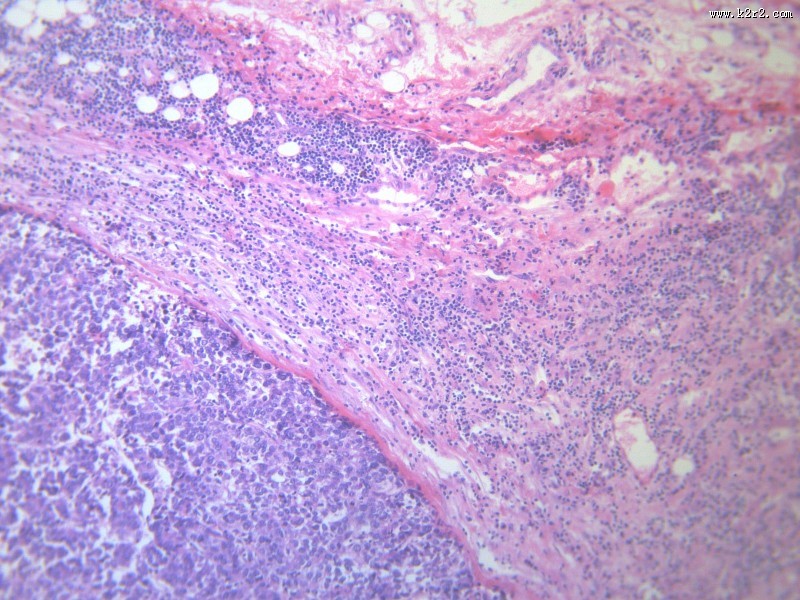

淋巴结内转移癌 - 第10张

淋巴结内转移癌

图集中 / 共有 12 张图片